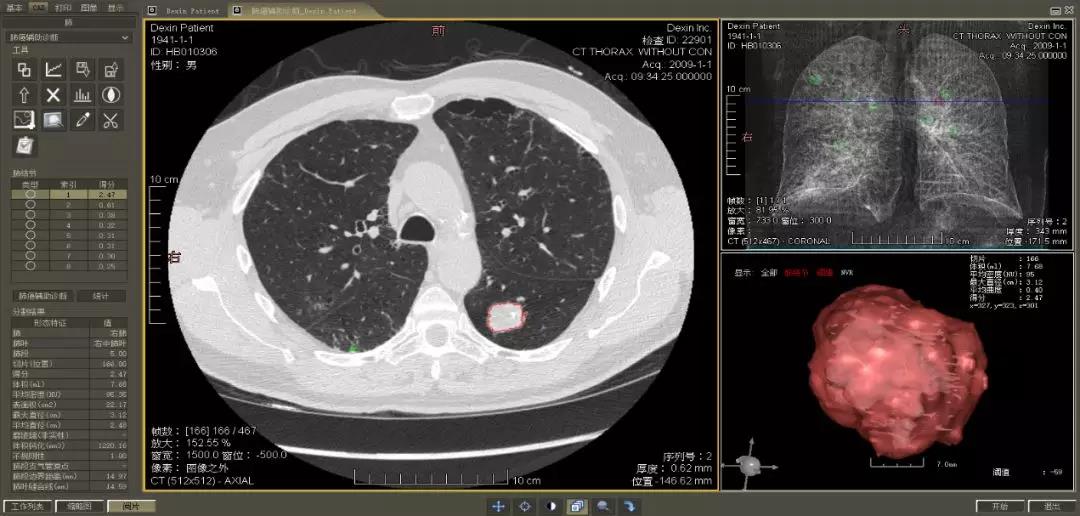

▲ 數(shù)字肺產(chǎn)品肺癌計(jì)算機(jī)輔助診斷

醫(yī)療影像智能分析是指運(yùn)用人工智能技術(shù)、計(jì)算機(jī)視覺技術(shù)以及計(jì)算幾何技術(shù)對(duì)醫(yī)療影像進(jìn)行自動(dòng)分析,幫助醫(yī)生定位病癥、分析、跟蹤病情,并通過量化數(shù)據(jù)輔助醫(yī)生做出診斷,目前其旗艦產(chǎn)品“數(shù)字肺”已經(jīng)覆蓋多種肺部疾病的早期檢測(cè)、診斷、跟蹤、術(shù)前規(guī)劃等完整的醫(yī)療流程。在臨床實(shí)踐中,超過80%的醫(yī)療數(shù)據(jù)來自醫(yī)療影像,這些影像數(shù)據(jù)通常需要專業(yè)醫(yī)生進(jìn)行解讀,工作的重復(fù)性高、效率偏低。如果能夠運(yùn)用智能影像分析技術(shù),同時(shí)結(jié)合臨床表現(xiàn)以及既往病例進(jìn)行全面分析,那么就可以大幅度提升影像診斷效率和準(zhǔn)確性,讓專業(yè)醫(yī)生的寶貴時(shí)間集中在復(fù)雜病情的診斷和治療等環(huán)節(jié)。